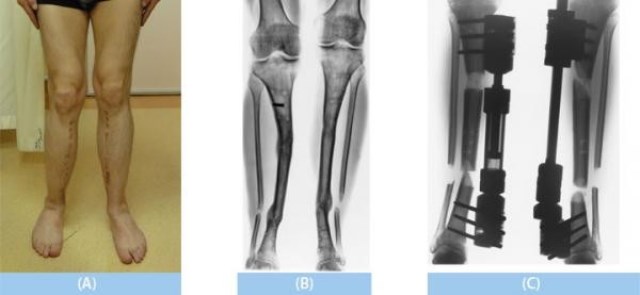

İkiye kırılan ayak kemikleri arasına açılan bir boşluk metal çubukla tutturuluyor ve günde 1 milimetre civarı çekerek uzatma yapılıyor. Hasta istediği uzunluğa ulaştığında işlem sonlanıyor ve bu bölgede yeni kemik dokusu oluşuyor.

Ancak iyileşme süreci aylarca devam ediyor. Hasta yeniden ayağa kalkabilmek için yoğun bir rehabilitasyon süreci geçiriyor.

Boy uzatma ameliyatı küçük sorunlardan çok ciddi sorunlara kadar yol açabilir. Hatta ayakların işlevlerini geçici ya da sürekli olarak kısıtlayabilir. Ameliyattan sonra sorun oluşursa, sorunu ortadan yok etmek için tedavi olmaları gerekiyor. Ekstra tedavi gerekiyor. Bu ekstra tedavi daha fazla zaman gerektiriyor ve ameliyat olmak da gerekir. Boy uzatma ameliyatı, ameliyatın yapılacağı kliniğe, konumuna ve ameliyatı yapacak doktora göre değişiklik gösterebilir. Boy uzatma ameliyatının sonucu olarak 6 santimetreden 12 santimetreye kadar varan boy artışı görülebilir. Sonuç daha çok bu ameliyat için bütçe gerekli ve zaman ayırmanız gerekli, ayrıca ağrıyla mücadele etmeniz gerekli, hareket kısıtlaması ve diğer rahatsız edici durumlarla nasıl başa çıkacağınıza bağlıdır.